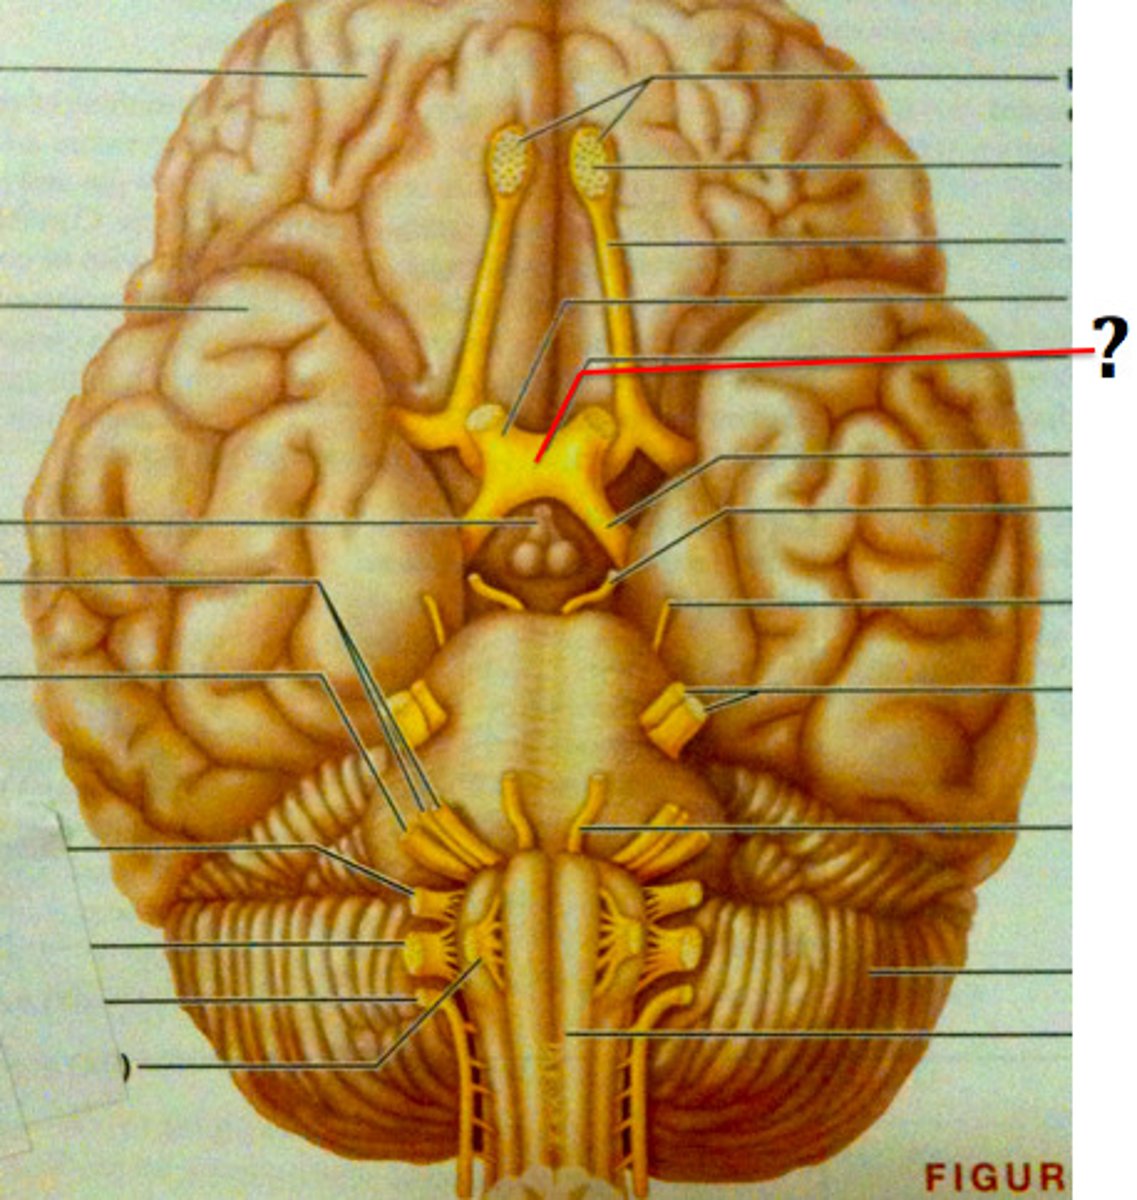

olfactory bulbs

olfactory tracts

double check this

optic nerves (cranial nerve II)

optic chiasma

optic tracts

CNIII (oculomotor nerve)

CNIV (trochlear nerve)

CNVI (abducens nerve)

infundibulum

pituitary gland

mammillary bodies